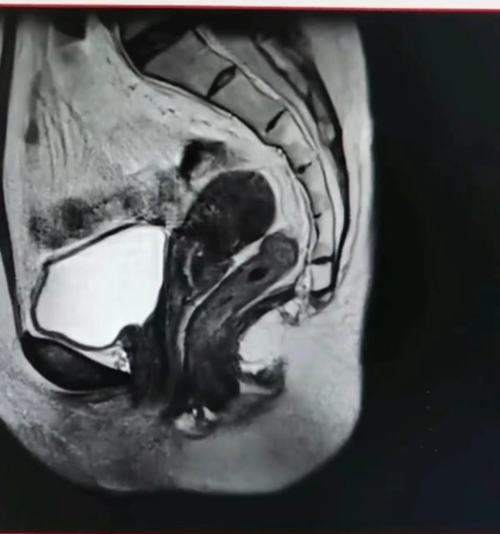

门诊查白带、HPV、TCT结果未见异常。2024-5-8宫腔镜下诊刮内膜病检示:子宫内膜不典型增生伴局部癌变。免疫组化:PTEN(+),PAX-2(-),MLHI(+),P53(突变型表达),Ki67(热点区约75%+),PMS2(+),MSH2(+),MSH6(+),ER(90%强+),PR(80%中等-强+),CD10(局部问质-),P16(部分+),CEA(-)。入院后完善各项检查,盆腔增强MRI示:子宫后位,前壁结合带信号不均匀,局部内膜凹凸不平,浸润深度>1/2肌层,子宫浆膜层完整,子宫多发肌瘤,盆腔少量积液,未见淋巴结肿大。上、下腹、盆腔增强CT,胸部CT未见明显异常、血常规、血脂、肝肾功能、生化、凝血、心电图、肿瘤标志物等结果均未见明显异常。

盆腔MRI: